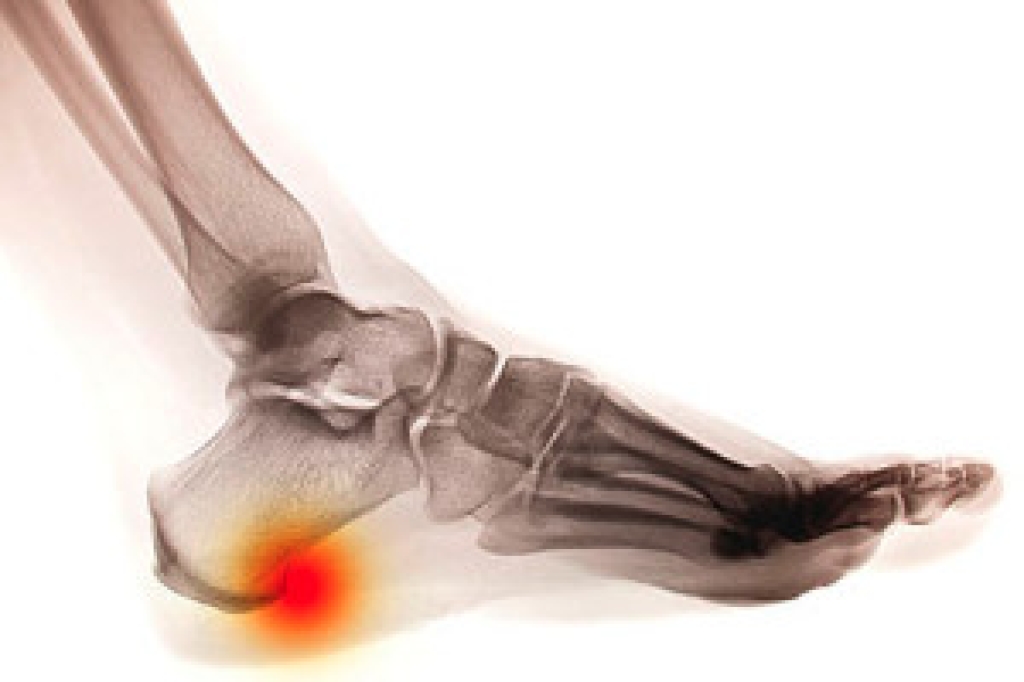

Stress and tension on the heels may result in a heel spur forming. It is defined as a small bony growth that forms on the bottom of the heel and is the body's natural defense against heel damage. The pain from a heel spur can be uncomfortable and can travel to the bottom of the foot where the plantar fascia lies. This is the band of tissue that connects the heel to the toes, and plantar fasciitis may gradually develop if inflammation occurs. A heel spur may be misdiagnosed as plantar fasciitis because it affects the heel. A proper evaluation is needed to differentiate between the two conditions, and this consists of having an X-ray taken. The heel spur is often noticeable in the X-ray and is done so the proper treatment can begin. Heel spurs can develop for various reasons, including wearing shoes that do not fit correctly, being overweight, or if the muscles in the back of the leg are tight. Mild relief may be found when comfortable shoes are worn, in addition to performing specific stretches that can ease heel pain. If you have a heel spur, please confer with a podiatrist as quickly as possible who can determine what the best treatment is for you.

Heel spurs are formed by calcium deposits on the back of the foot where the heel is. This can also be caused by small fragments of bone breaking off one section of the foot, attaching onto the back of the foot. Heel spurs can also be bone growth on the back of the foot and may grow in the direction of the arch of the foot.